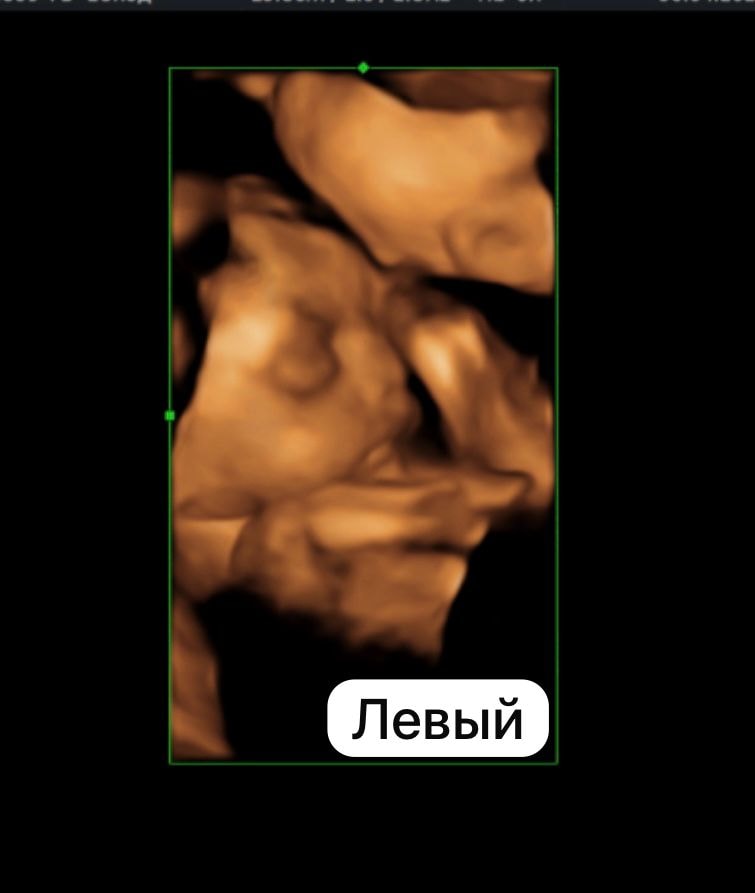

Идем пока ровно 🥰 оба головой вниз . Вес левого - 1148 , вес правого - 1159 . Срок 28,3.

Левый у вас явно будет большой начальник, сразу видно грозного руководителя)))

Вериока, ахах )) точно

Ну он и ведет себя более ответственно) всегда отвечает на вопросы . А правый молчун